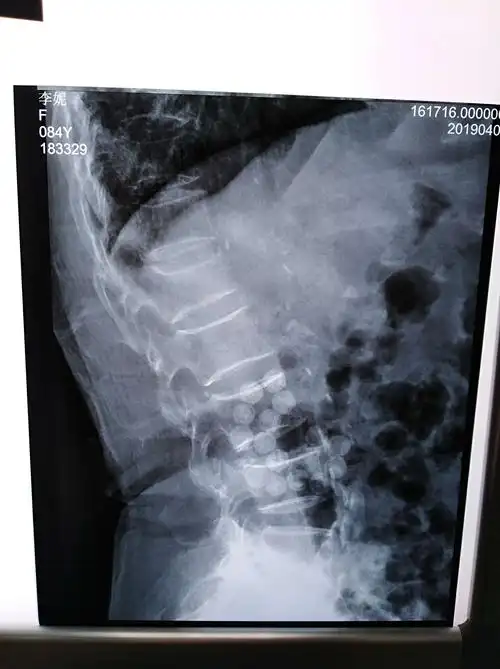

腰椎第一节骨折能评几级伤残 交通事故腰椎第一节压缩性骨折是几级

腰椎压缩性骨折新鲜

老年骨质疏松伴腰1椎体压缩性骨折

腰1椎体压缩性骨折(3度)

术前腰椎mri显示腰1椎体新鲜压缩骨折

腰1椎体陈旧性压缩骨折,后突畸形!行后路矫形术后! (原创)

术前dr示腰1椎体压缩骨折

平谷中医院 骨1科 一例腰椎压缩骨折术前术后片对比

老年性腰1椎体再次压缩性骨折的经皮椎体成形术

腰椎平片提示腰1椎体前缘压缩有二分之一,侧位片非常明显,且腰椎ct